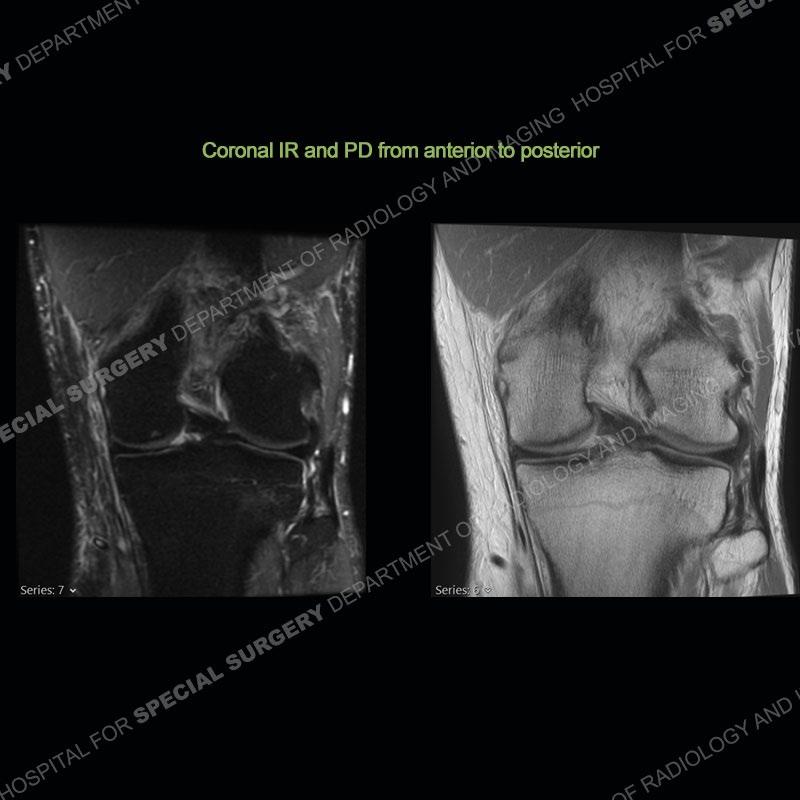

The radiographs show degenerative change of the medial compartment and a varus knee, but they are not germane to this case. No acute bony injury is present. The MRI shows edema of the posterior medial knee/soft tissue and a focal area of a partially disrupted low signal structure. The details are kept at a minimum in the findings of this case on purpose.

Fourth, use all imaging planes and different pulse sequences to make your diagnosis. The edema highlighted in this case can be seen as the obscuration of fat on the PD images but is much easier to perceive as the high signal on the IR pulse sequences. The actual disruption of the MHG myotendinous junction is only able to be seen on the axial images. On the sagittal and coronal images, we get a sense something is wrong but hard to be exact. Lastly, when you look at a study and something just seems off (as I would say the sagittal and coronal images do with that dark band of tissue posteriorly), listen to yourself and go through the study slowly and meticulously. Most of the time you will find you were right, and something indeed is present.